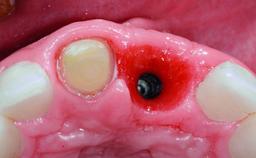

Replacement of an Upper Right Central Incisor with Root Resorption: Ridge Preservation, Delayed Placement of an NC Bone Level Roxolid Implant

A 32-year-old female Caucasian patient with a compromised maxillary right central incisor was referred to us by a general dentist. Her chief complaints were discomfort and mobility of tooth 11 with unsatisfactory esthetics due to discoloration. The patient reported a previous trauma, some years earlier, as the origin of pathology on the afflicted tooth. Anamnesis was negative for any other dental or periodontal pathology in the remaining dentition. The patient did not take any medication and reported to be a light smoker (5–10 cigs/day). She had high esthetic expectations of her treatment. The extraoral examination revealed a high smile line with full exposure of her maxillary teeth and surrounding soft tissue in the area between the second premolars.

Bone Augmentation Horizontal|Simultaneous|Staged

Augmentation Materials Autogenous chips|Xenogenous|Membrane

Bone Volume Deficient horizontally, requiring prior grafting